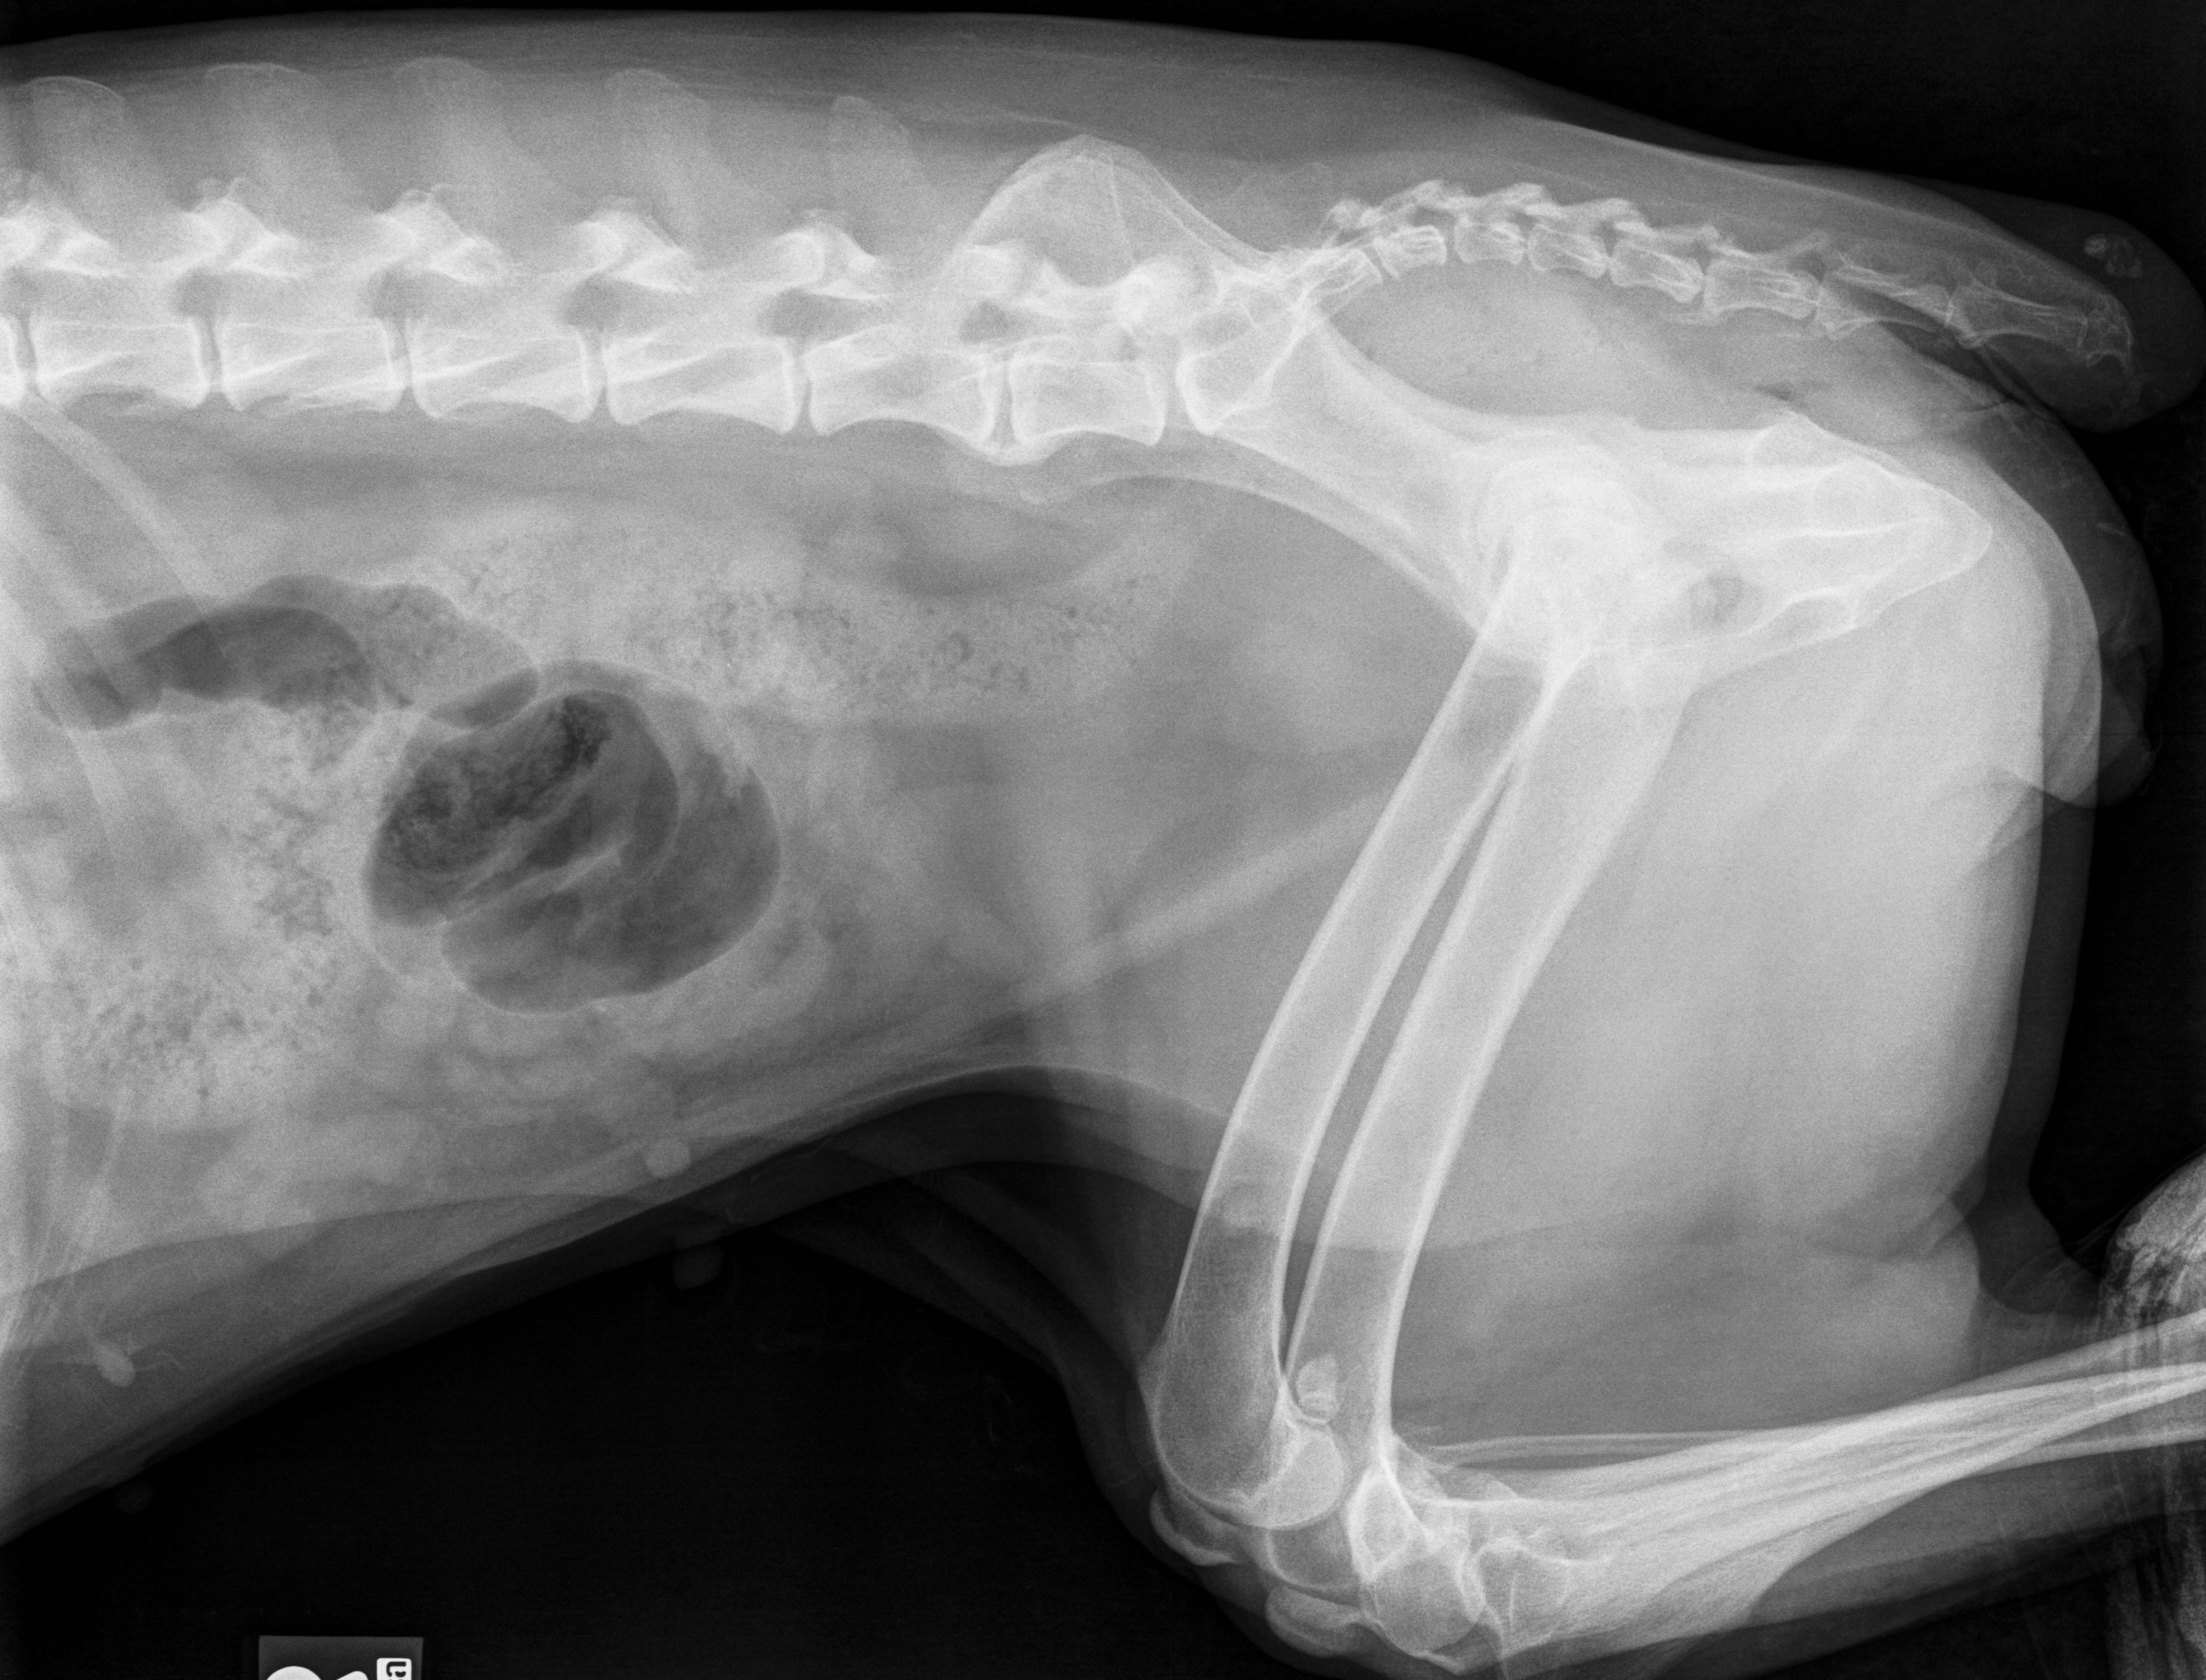

Latérale droite caudale